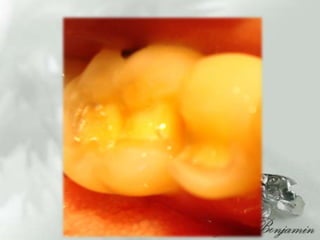

DIAGNOSTICOAparatos y sistemas:  Refiere :Antecedentes de Calculos Biliares , Intervencionquirugica aproximadamente hace 10 años    Bronquitis, aproximadamente hace 5 añosAntecedentes heredofamiliares 3 Hermanos con diabetes tipo II, Gingivitis Zona dientes anteriores inferioresLesiones cariosas grado I (24.25.27, 34)Restauraciones desajustadas (37,38,47,48,25, 26)  Oclusionismo  aproximadamente 15 años

Plan de tratamientoFASE IDesprogramación muscular , terapia oclusal, (guarda oclusal) FASE IIOperatoria dental en dientes: AmalgamasResinasIncrustacionesPujanaGarcia Salmones JoseAgustin, Et, al, Oclusion tratado de teoria y practica para el odontologo  2009Martinez Ross Erik Et, Al, OclusionOrganica y  Ortognatodoncia,  2009PegoraroLuiz Fernando, Et al, Protesis Fija  2001

Plan de tratamientoFASEIDesprogramación muscular , terapia oclusal, (guarda oclusal) FASE IIOperatoria dental en dientes: AmalgamasResinasIncrustacionesPujanaGarcia Salmones JoseAgustin, Et, al, Oclusion tratado de teoria y practica para el odontologo 2009Martinez Ross Erik Et, Al, OclusionOrganica y Ortognatodoncia, 2009PegoraroLuiz Fernando, Et al, Protesis Fija 2001